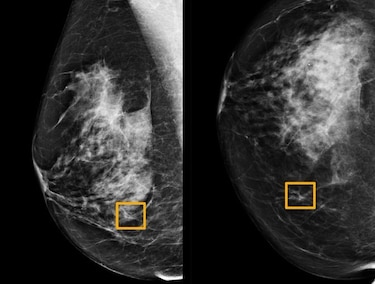

Un programa informático mostró una mejor precisión que los expertos radiólogos para identificar cáncer de mama a partir de imágenes de mamografía, según un estudio británico.

Esta técnica de inteligencia artificial (IA), fruto de la investigación de Google, se basa en un modelo matemático, un algoritmo. Este último fue ensayado, alimentado, con cerca de 29,000 imágenes de mamografías del Reino Unido y, en menor medida, de Estados Unidos.

La IA mostró una reducción de la proporción de casos en los que se detectaba erróneamente un cáncer, de 5.7% de las imágenes estudiadas de Estados Unidos y de 2.7% entre las británicas.

El algoritmo también disminuyó el porcentaje de diagnósticos fallidos: un 9.4% entre las imágenes de Estados Unidos y un 2.7% entre las del Reino Unido.